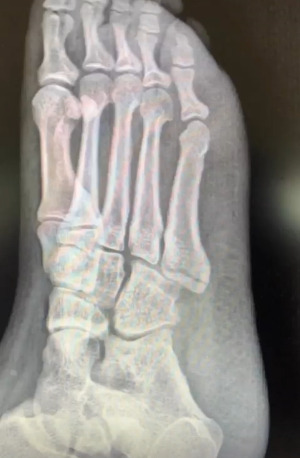

수술 일주일 전 병가 전 마지막 출근 날 나는 만취해 욕조에서 미끄러져 오른쪽 발바닥이 부러졌다.

KakaoTalk_20250604_125631661.jpg 그날의 부러진 발을 추억하며